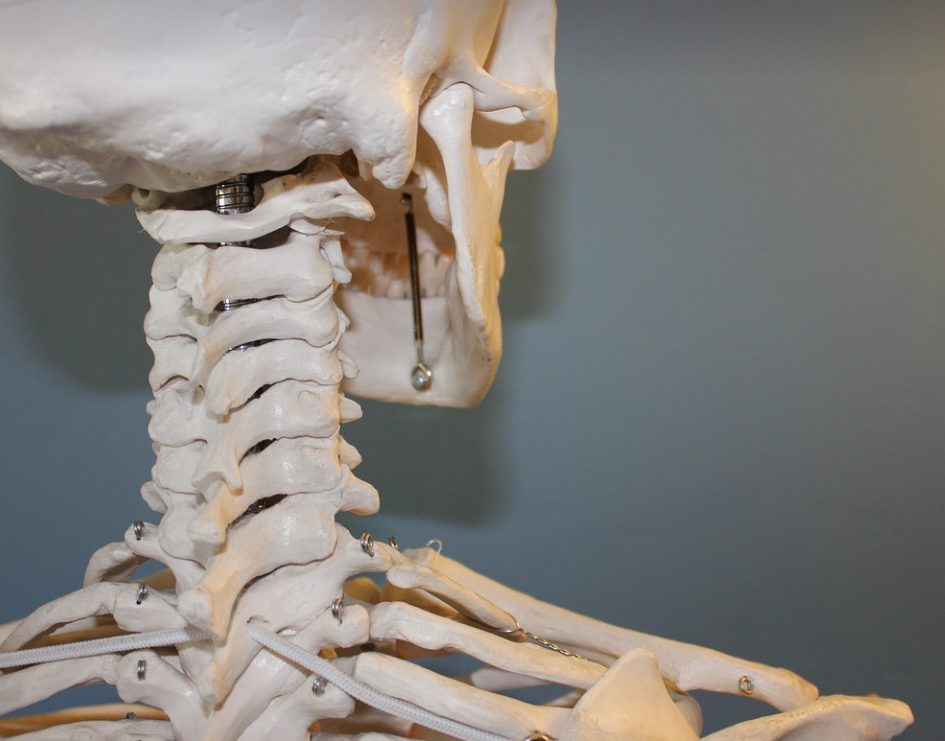

🦴 골다공증이란? 왜 위험할까요?

골다공증은 뼈의 밀도가 감소하고 구조가 약해져 쉽게 골절될 위험이 높은 질환입니다.

특히 나이가 들면서 뼈가 약해지는 자연스러운 과정이지만, 일부 요인에 의해 더 빠르게 진행될 수 있습니다.

- 척추뼈, 손목, 고관절 골절 위험 증가

- 심한 경우 허리뼈가 무너져 압박골절이 생길 수도 있음